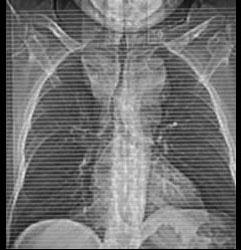

男,41岁,体检X线提示纵隔增宽,CT检查如图,请选出最可能的诊断 ( )A、间皮囊肿B、胸内甲状腺肿C、纵隔畸胎瘤D、胸腺瘤E、淋巴瘤

问题 男,41岁,体检X线提示纵隔增宽,CT检查如图,请选出最可能的诊断 ( )

选项 A、间皮囊肿 B、胸内甲状腺肿 C、纵隔畸胎瘤 D、胸腺瘤 E、淋巴瘤

答案 B